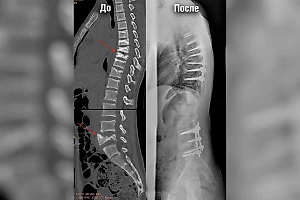

«Диагностика показала открытый перелом двух костей со смещением отломков. Потребовалась операция. Мы восстановили правильное анатомическое положение костей с помощью фиксации стержнями», — рассказал врач – травматолог-ортопед Александр Нестеренко.

Операция прошла успешно, сейчас мальчик восстанавливается дома. Его ждёт длительный реабилитационный период. А затем, после полного восстановления, ему удалят металлические спицы.